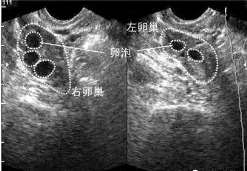

卵泡(follicle)是由卵巢皮质内的一个卵母细胞和其周围许多小的卵泡细胞所组成,每个月排卵的时分,两个卵巢 […]

多少个卵泡算多囊

正常老练卵泡的巨细规范: 一般来说,正常老练的卵泡巨细在18-25毫米之间,但每个人的状况都不相同,卵子何时排 […]

正常成熟卵泡的大小标准达到多少毫米才能排出